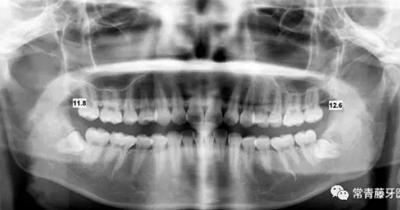

影像學檢查

曲斷顯示38、48阻生;雙側(cè)TMJ髁突頭略不對稱。

頭影測量顯示上下頜骨發(fā)育不足,且呈現(xiàn)骨性Ⅱ類。

曲斷可見牙根基本平行。